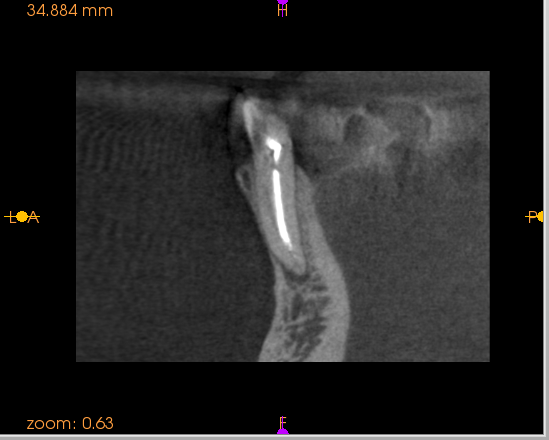

EMR(根幹長測定器)で根尖はかれない症例。CT撮影

おわかりいただけるだろうか?根尖が3股に分かれている上に、側枝あり。

リーマー・ファイルでは3根管を洗浄できない。

そこで、バイブリンジ、エンドアクチベーターが役立ちます。